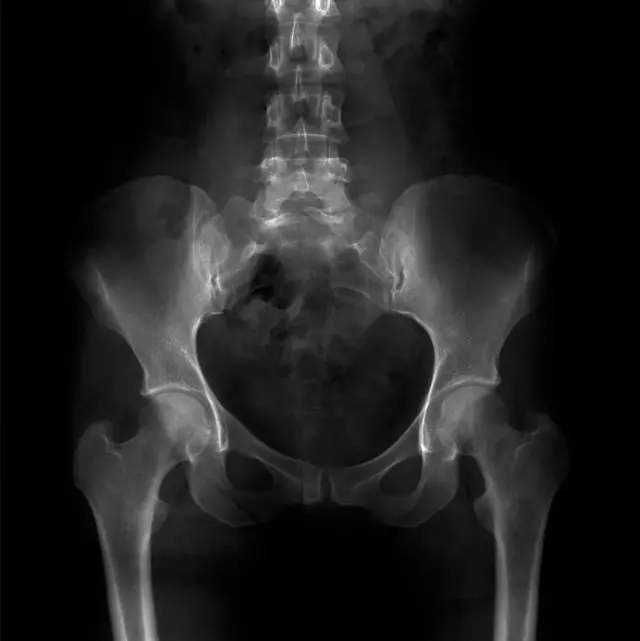

ਖੋਜ ਦਲ ਨੇ ਕੁਝ ਅਜੀਬ ਵੀ ਦੇਖਿਆ। ਉਨ੍ਹਾਂ ਨੇ ਦੇਖਿਆ ਕਿ ਜੇ ਕੋਈ ਚੂਹਾ ਸਿਰਫ਼ ਉਸੇ ਟੀਬੀਐੱਕਸਟੀ ਜੀਨ ਨਾਲ ਤਿਆਰ ਕੀਤਾ ਜਾਵੇ ਜਿਸ ਵਿੱਚ ਸਿਰਫ਼ ਉਹ ਗੈਰ-ਹਾਜ਼ਰ ਹਿੱਸਾ ਹੀ ਹੋਵੇ। ਇਸ ਨਾਲ ਉਹ ਚੂਹੇ ਪੈਦਾ ਹੋਏ ਜਿਨ੍ਹਾਂ ਵਿੱਚ ਮਨੁੱਖਾਂ ਵਰਗਾ ਜਮਾਂਦਰੂ ਵਿਕਾਰ ਦੇਖਿਆ ਗਿਆ— ਸਪਾਈਨਾ ਬਾਈਫਾਈਡਾ (ਜਦੋਂ ਕੁੱਖ ਵਿੱਚ ਰੀੜ੍ਹ ਦਾ ਵਿਕਾਸ ਮੁਕੰਮਲ ਨਹੀਂ ਹੁੰਦਾ ਅਤੇ ਰੀੜ੍ਹ ਵਿੱਚ ਫਰਕ ਰਹਿ ਜਾਂਦਾ ਹੈ।)

ਮਨੁੱਖੀ ਟੀਬੀਐੱਕਸਟੀ ਵਿੱਚ ਹੋਏ ਰੂਪਾਂਤਰਣਾਂ ਨੂੰ ਪਹਿਲਾਂ ਇਸ ਬੀਮਾਰੀ ਨਾਲ ਜੋੜਿਆ ਜਾਂਦਾ ਰਿਹਾ ਹੈ। ਇਹ ਵੀ ਦੇਖਿਆ ਗਿਆ ਕਿ ਚੂਹਿਆਂ ਵਿੱਚ ਰੀੜ੍ਹ ਦੀ ਹੱਡੀ ਅਤੇ ਸਪਾਈਨਲ ਕੌਰਡ ਨਾਲ ਜੁੜੇ ਹੋਰ ਵਿਕਾਰ ਵੀ ਸਨ।

ਤਸਵੀਰ ਸਰੋਤ, Getty Images

ਖੋਜ ਦਲ ਮੁਤਾਬਕ ਕਿ ਜਿਵੇਂ ਪੂਛ ਦੀ ਹੱਡੀ ਦਾ ਸਬੰਧ ਸਾਡੇ ਸਾਰਿਆਂ ਦੇ ਲੰਡੇ ਹੋਣ ਨਾਲ ਹੈ। ਉਸੇ ਤਰ੍ਹਾਂ ਸਪਾਈਨਾ ਬਾਈਫਾਈਡਾ ਵੀ ਜੀਨ ਵਿੱਚ ਆਏ ਉਸ ਦੁਰਲੱਭ ਬਦਲਾਅ ਦਾ ਨਤੀਜਾ ਹੋ ਸਕਦੀ ਹੈ, ਜੋ ਸਾਡੇ ਲੰਡੇ ਹੋਣ ਲਈ ਜ਼ਿੰਮੇਵਾਰ ਹੈ।

ਸਪਾਈਨਾ ਬਾਈਫਾਈਡਾ- ਜਦੋਂ ਕੁੱਖ ਵਿੱਚ ਰੀੜ੍ਹ ਦੀ ਹੱਡੀ ਦਾ ਵਿਕਾਸ ਠੀਕ ਨਹੀਂ ਹੁੰਦਾ ਅਤੇ ਉਸਦੇ ਅੰਦਰੋਂ ਗੁਜ਼ਰਨ ਵਾਲੀ ਸਪਾਈਨਲ ਕੋਡ ਗੁੱਛੇ ਦੇ ਰੂਪ ਵਿੱਚ ਬਾਹਰ ਨਿਕਲ ਆਉਂਦੀ ਹੈ। ਇਹ ਰੀੜ੍ਹ ਦੀ ਹੱਡੀ ਦੇ ਪੂਰੇ ਖੇਤਰ ਵਿੱਚ ਕਿਤੇ ਵੀ ਪੈਦਾ ਹੋ ਸਕਦੀ ਹੈ ਅਤੇ ਆਪਣੇ ਤੋਂ ਹੇਠਾਂ ਵਾਲੇ ਹਿੱਸੇ ਦੇ ਅੰਗਾਂ ਦੀ ਸਮਰੱਥਾ ਨੂੰ ਪ੍ਰਭਾਵਿਤ ਕਰਦੀ ਹੈ।

ਸਾਇੰਸਦਾਨ ਕਹਿੰਦੇ ਹਨ ਕਿ ਲੰਡੇ ਹੋਣ ਦੇ ਫਾਇਦੇ ਸਪਾਈਨਾ ਬਾਈਫਾਇਡਾ ਦੇ ਨੁਕਸਾਨਾਂ ਨਾਲੋਂ ਜ਼ਿਆਦਾ ਸੀ। ਇਸ ਲਈ ਇਹ ਖਤਰਾ ਚੁੱਕਿਆ ਜਾ ਸਕਦਾ ਸੀ।